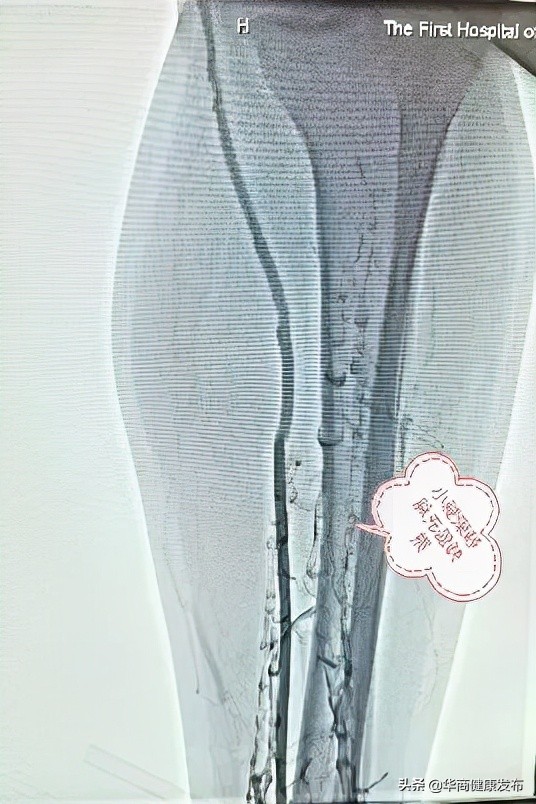

那日,小劉像往常一樣跑步鍛鍊,期間,他不小心扭到了腳踝,便回家臥床休息。沒想到,一天後,他的左下肢出現明顯腫痛症狀。在家人的陪同下,他來到西安醫學院第一附屬醫院就診,經過詳細檢查之後,小劉竟被確診為“急性下肢深靜脈血栓”。

“正常的下肢血液是經靜脈向心髒迴流,下肢深靜脈血栓形成(DVT)是指血液非正常的在深靜脈內凝結,引起的靜脈迴流障礙性疾病。患者此次可能就是因為臥床休息,未活動,導致深靜脈血栓形成。當靜脈內血栓形成,血液迴流受阻,下肢就會開始出現腫脹、腫痛症狀。如果沒有得到及時有效治療,下肢血栓脫落可引起肺動脈栓塞,患者會出現呼吸困難,嚴重時會導致心跳、呼吸驟停,死亡率高達9%-50%。”普通外科副主任醫師李武軍介紹。

為防止致命的肺栓塞發生,普通外科外周血管團隊為小劉制定了血管腔內治療及藥物溶栓的微創治療方案。

在我院外周血管團隊醫護人員的密切配合下,緊急為小劉進行了腔靜脈濾器置入+導管吸栓溶栓微創治療。

手術順利結束,及時解除了危及患者生命的因素。結合術後系列治療,小劉下肢腫脹情況明顯好轉,經過造影複查,下肢血栓全部消除,現已痊癒出院。